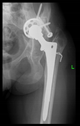

The radiological examination allowed us to verify the close bone-to-implant contact and the unchanged position of the implant during follow-up.

In all the cases operated with the above-described targeting procedure, the stems of the cups remained between the cortical bone surfaces without perforation of the linea terminalis, as shown by postoperative radiographs. There were no complicated surgical situations. In 16 cases, the wound healings were uneventful, and the hips were able to bear weight again after postoperative rehabilitation.